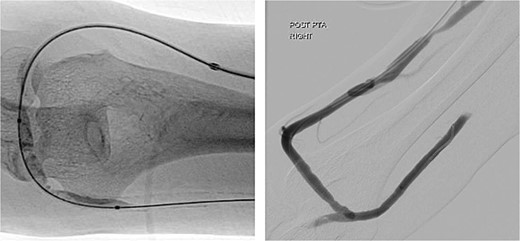

During the procedure, juxta-anastomotic and anastomotic stenoses of up to 75% were treated using non-compliant Mustang™ (Boston Scientific) balloon catheters (5 × 40 mm and 6 × 40 mm), inflated serially at 20 atm for 2 minutes each (Fig. 2). There was an improved palpable thrill after the angioplasty.

Angioplasty of the arteriovenous fistula 2 days prior to clinical presentation.